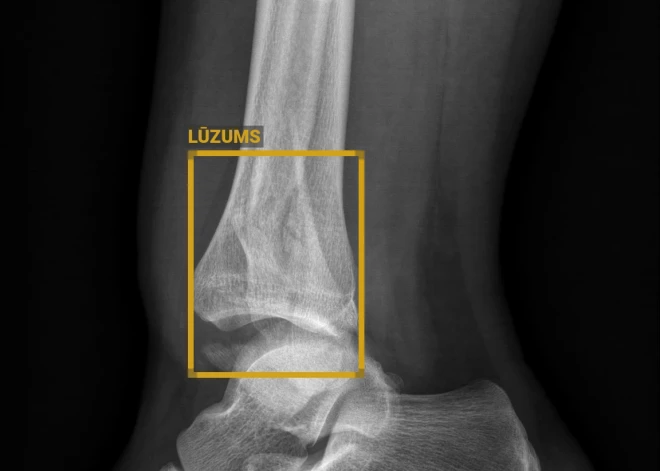

Uzlabojot pakalpojumu kvalitāti, Vidzemes slimnīca turpina ieviest mākslīgā intelekta risinājumus. Jaunākais no tiem ir saistīts ar diagnostiskajiem izmeklējumiem, kuros tiek iesaistīts digitālais rentgena attēlu mākslīgā intelekta apstrādes rīks “GLEMER BoneView”. Tas atklāj kaulu lūzumus, arī izsvīdumus, dislokācijas un kaulu bojājumus rentgena attēlos, informē Vidzemes slimnīca.

“Radiologu un citu speciālistu, kuru ikdiena saistīta ar dažādu kaulu traumu atpazīšanu un ārstēšanu, uzticams un precīzs palīgs. Ir pierādīts, ka šis palīgs uzlabo diagnostikas laiku un samazina kļūdu iespējamību. Mākslīgais intelekts, protams, neaizstāj cilvēku, bet kalpo kā attēla dubulta pārbaude un ievērojami samazina cilvēciskās kļūdas riskus, nosakot diagnozi. Atpazīšanas precizitāte, kā liecina pētījumi, sasniedz 97 līdz 99 % atkarībā no anomālijas,” uzsver Ciguzis.

BoneView ir apstiprināts klīniskai lietošanai gan pieaugušo, gan bērnu izmeklējumiem, un tas palīdz samazināt diagnostikā garām palaistu lūzumu skaitu par 30%.